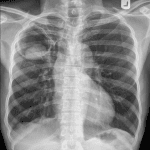

100 Ca X-Quang Ngực | Thực Hành

Thực hành đọc phim X-quang ngực.

100 Ca lâm sàng kèm chú thích mô tả tổn thương.